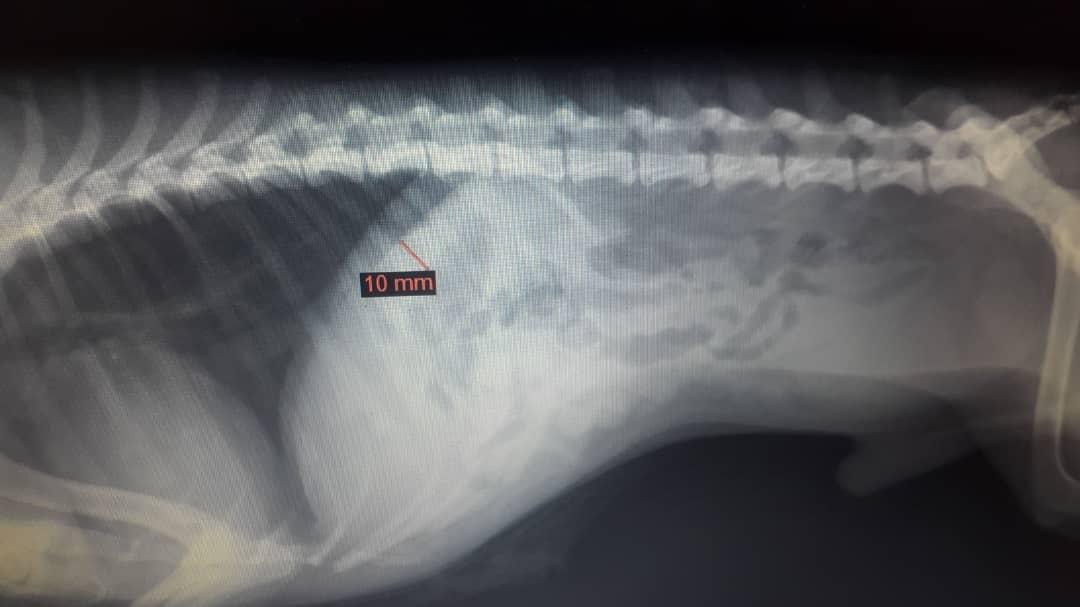

Hi. This substance is always on my dog’s penis, even if he’s just peed and I cleaned him. It doesn’t smell like anything, does pees normally, no signs of pain or struggle, pee usually is normal or is in an spraying action which I think is when he’s marking. He had X-rays a few weeks ago, which I’m attaching both substance and x-ray photo below. Is it worrying? What’s the substance? Is there anything unusual in his x-ray?